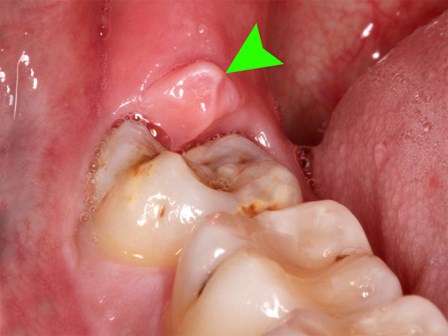

Răng số 8 có hay biến chứng? Khi nào biến chứng răng số 8 có thể gây tử vong?

Các bác sĩ tại Bệnh viện Răng Hàm Mặt trung ương thường xuyên phải cấp cứu cho các trường hợp bị áp xe trung thất, áp xe họng dẫn đến ngạt thở do biến chứng từ răng số 8.

Răng số 8 - răng khôn mọc... dại: Khi nào cần nhổ, nhổ có nguy hiểm không?

Theo các bác sĩ Bệnh viện Răng hàm mặt Trung ương, không có chuyện nhổ răng số 8 là bị tâm thần, ảnh hưởng tới thần kinh như dân gian vẫn nghĩ.